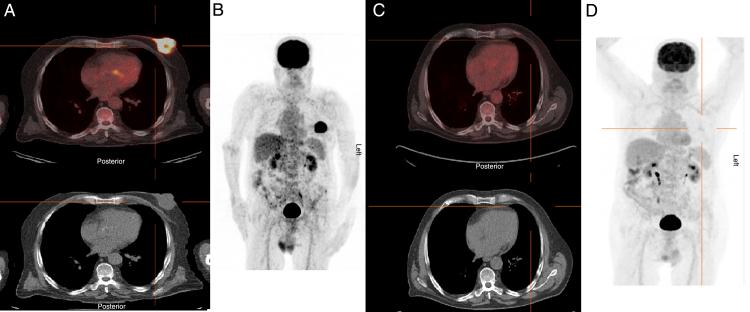

Primary breast lymphoma in a male patient.